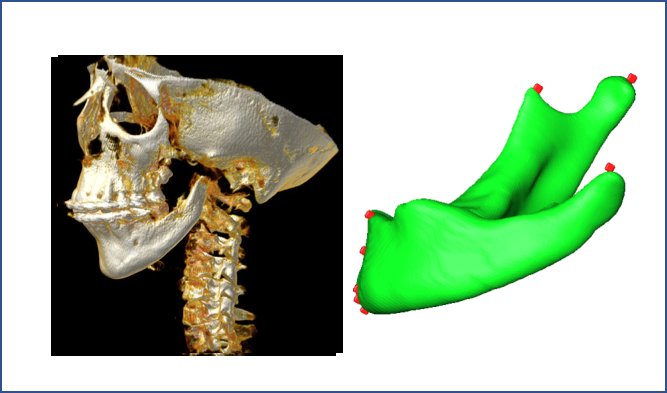

Note that these anatomical landmarks often reside on the same sagittal plane in the same order according to the mid-point of the lower-jaw incisors. We propose to capture this order dependence by using an LSTM architecture in the sagittal axis of the images containing the landmark “Menton” (Figure 6). The rationale behind this choice is that LSTM network is a type of RNN introduced by Hochreiter et al. [23] in 1997, modeling the temporal information of the data effectively. Although the imaging data that we used for landmark localization does not include temporal information in the standard sense, we modeled the landmark relationship as a temporal information due to their close positioning in the same plane. This phenomenon is illustrated in Figure 6. The input data to the LSTM network was a mandible binary boundary image of the sagittal plane of the landmark , and the output is a vector of 0’s and 1’s: while 0 refers to non-landmark location, 1 refers to a landmark location in the sagittal axis. Figure 7 shows further details of the LSTM network and content of a sample LSTM block that we used for effective learning of closely-spaced landmarks.

To generate the training data, the sagittal slice region containing the closely-spaced landmarks “Menton”, “Gnathion”, “Pogonion”, “B-point” and “Infradentale” is scaled into a binary boundary image of size . The landmark locations (marked by red circles in Figure 6) on this boundary image are parametrized as (x,y), where y is the row number in the range to , and x is the white boundary column number of the corresponding row y. Due to having training patients’ scans, there are only sagittal slices containing the closely-spaced landmarks, which is insufficient for the LSTM training. Hence, in order to increase the number training images, we performed Principal Component Analysis (PCA).